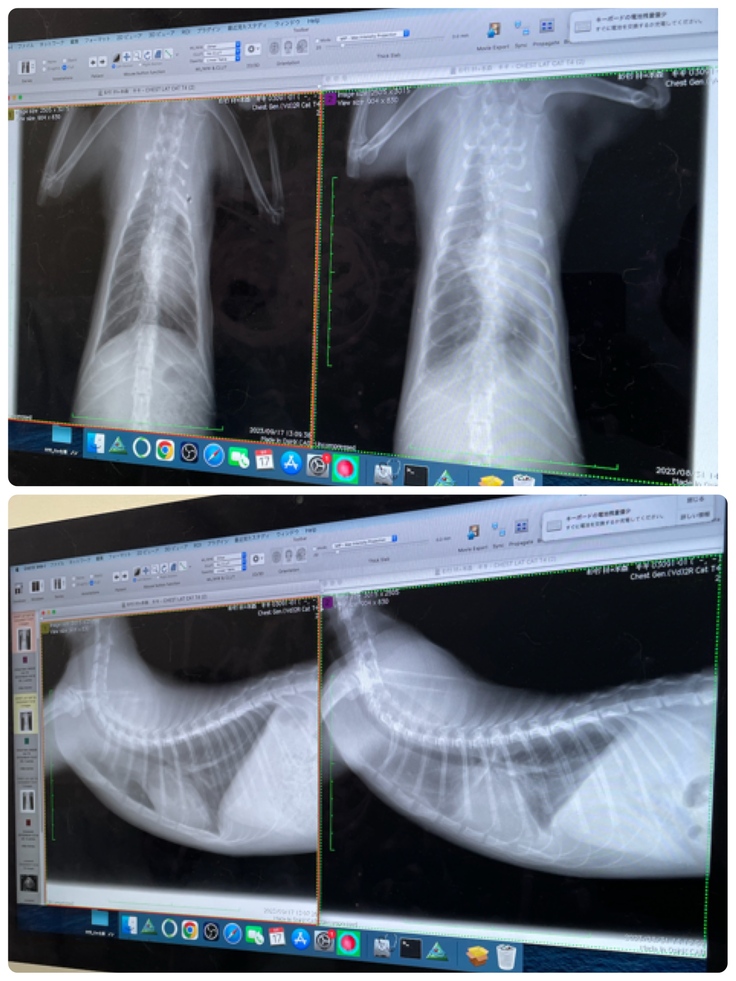

病院では採血とレントゲン検査を実施しました。

胸水もなくなってます。

右肺がまだ少ししろいけど、3週間前より劇的に良くなり、採血も貧血もSAAの数値もびっくりするくらい🥹